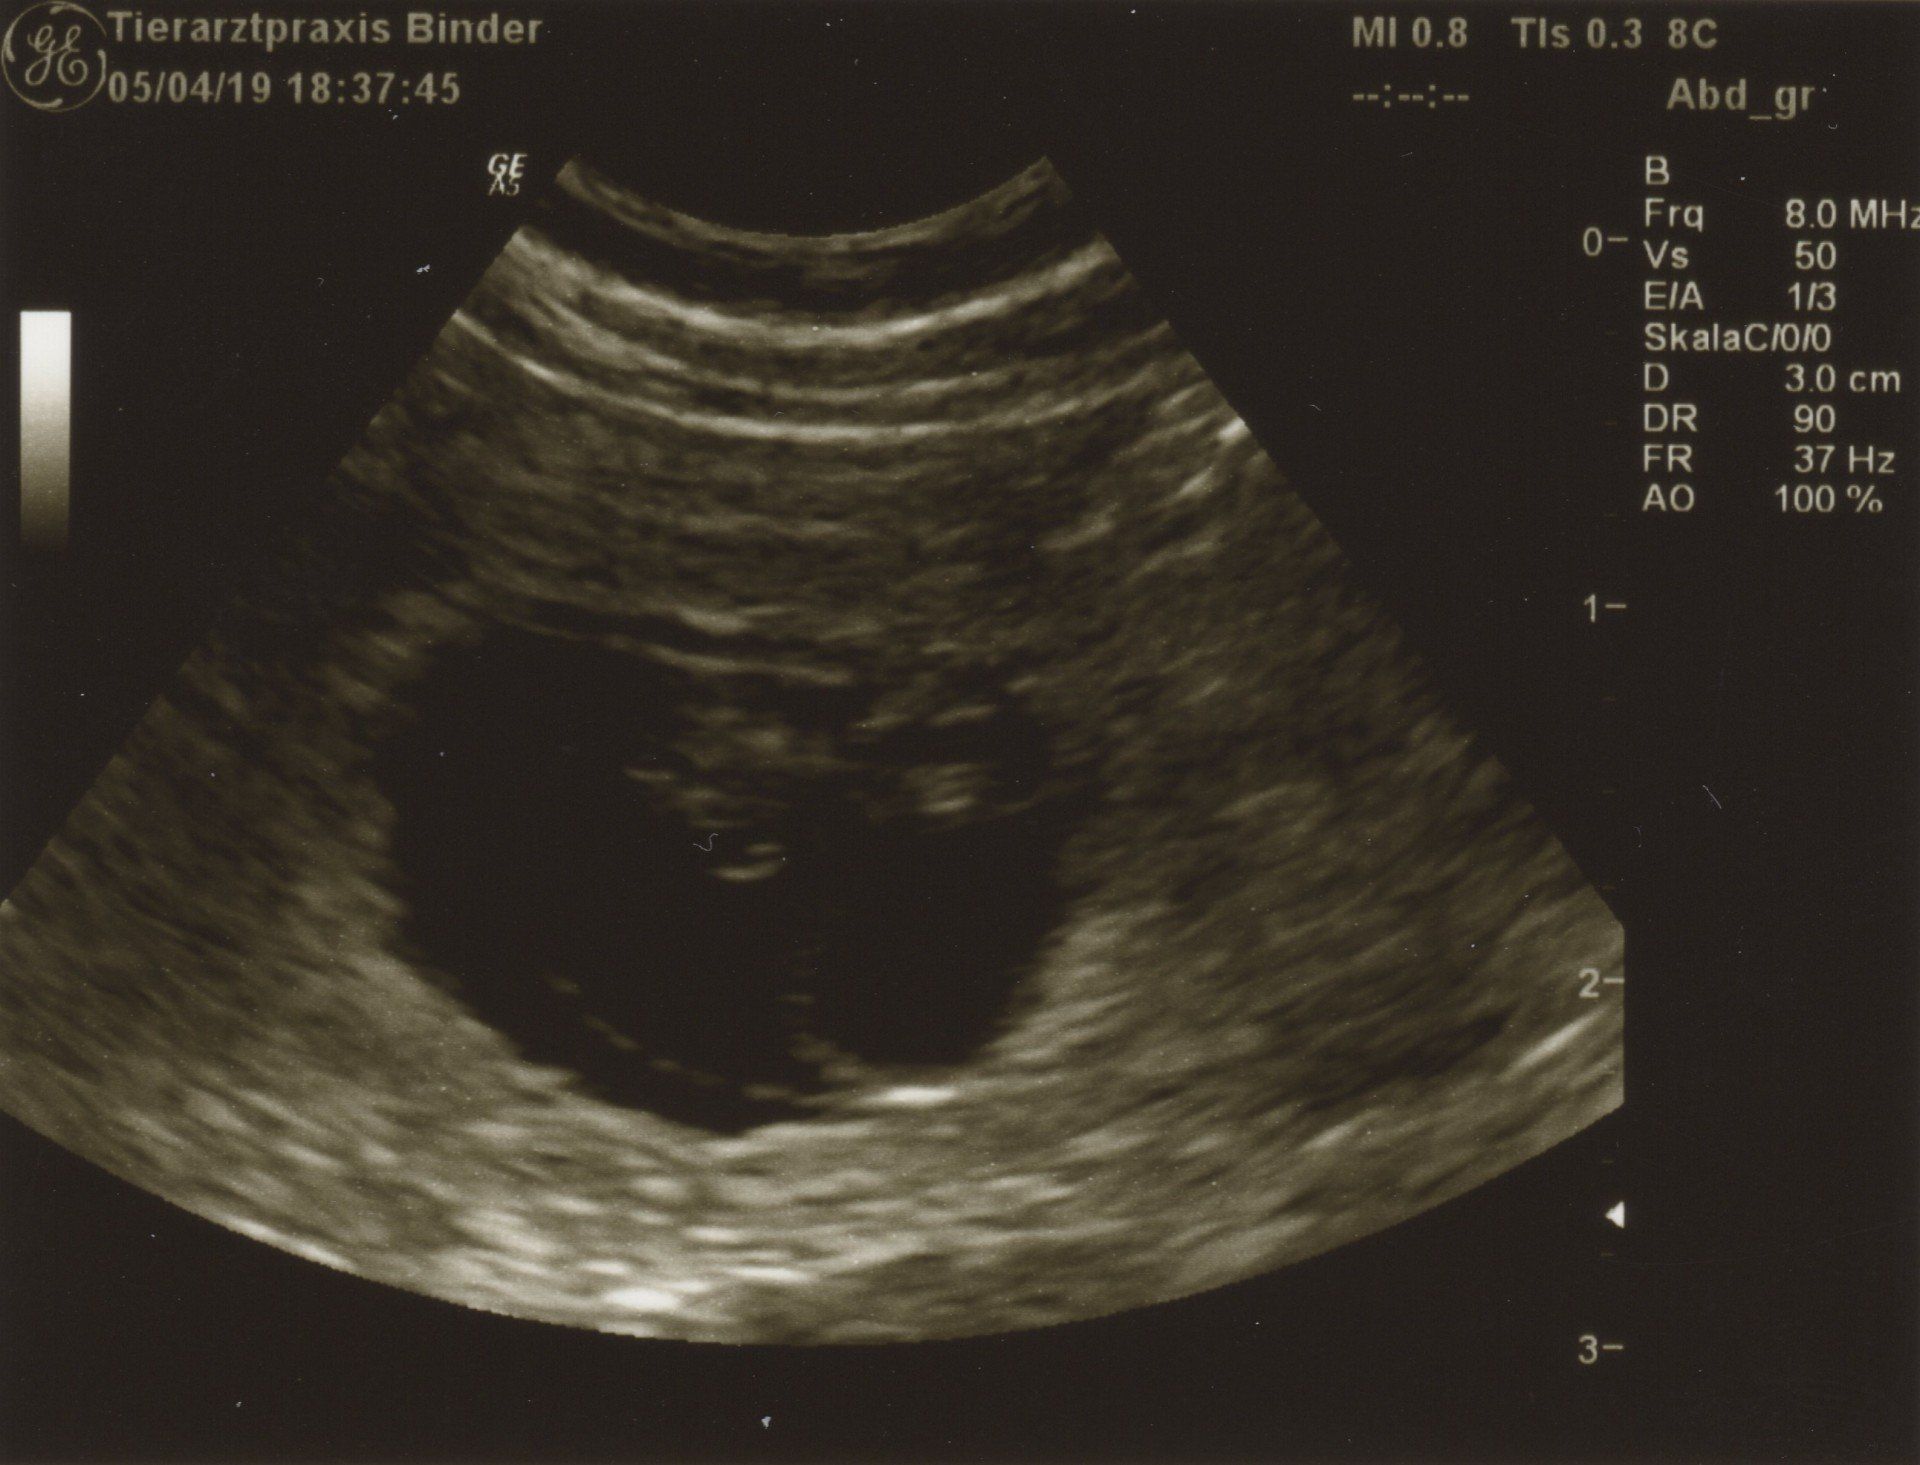

05.04.2019 Woche 4 25.Tag von ca.63Tagen

Tag 25 Ultraschall Untersuchung bei Dr. Binder

05.04.2019

Wir waren zur Ulraschalluntersuchung! Ja !